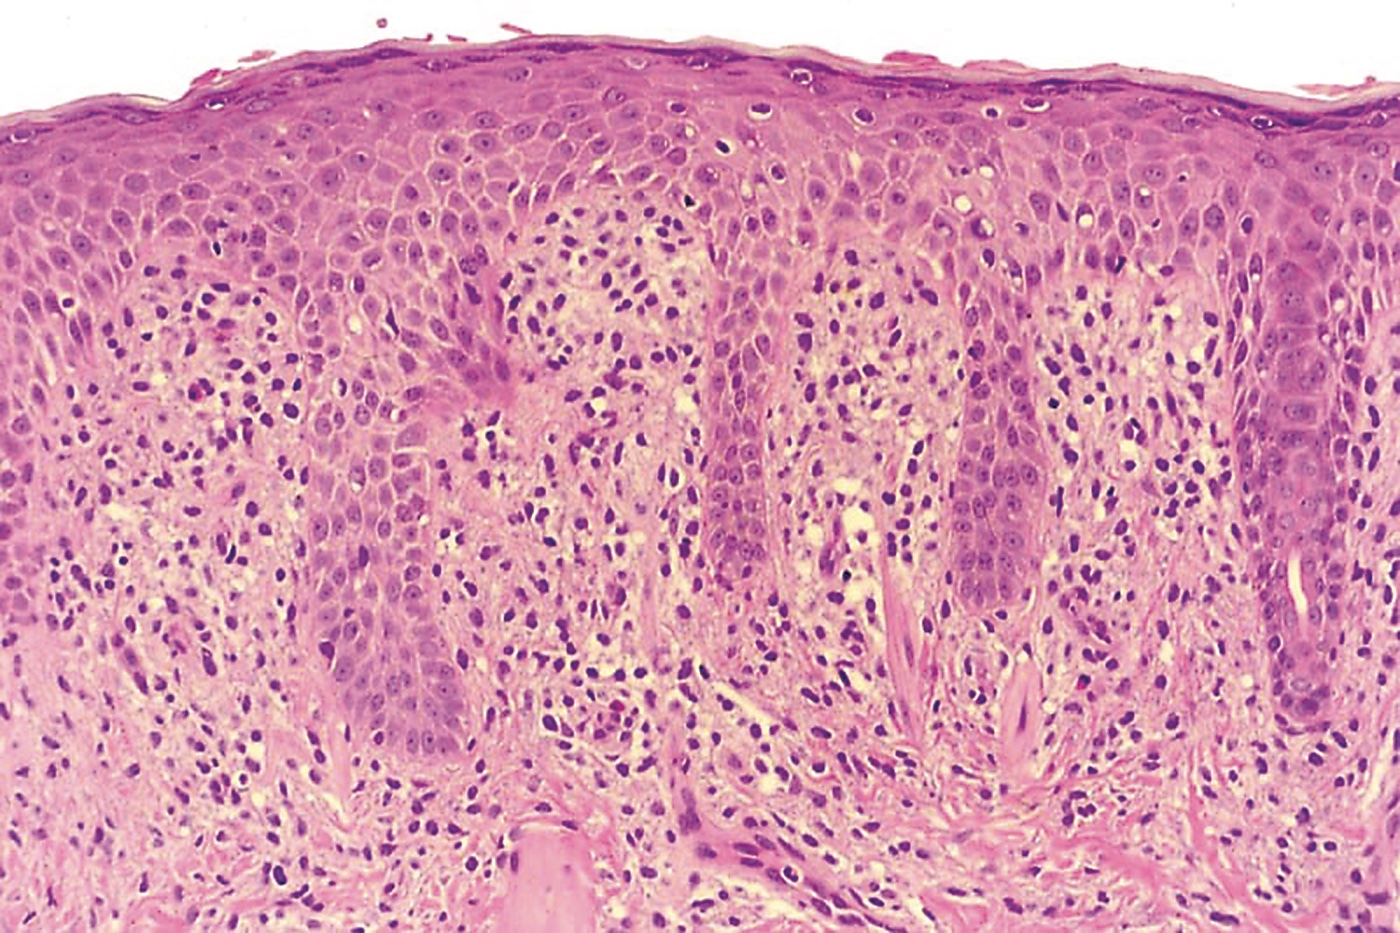

Solitary mastocytoma is usually a clinical diagnosis.4 Episodes of swelling and bulla formation are helpful diagnostic clues.3 The Darier sign is virtually pathognomonic for mastocytoses. Because the disseminated form may begin with a single lesion and dissemination usually occurs within 3 months of onset, the diagnosis of a solitary mastocytoma should not be made unless the single lesion has persisted for more than 3 months.3 Skin biopsy is usually only required in atypical cases.4 Histologically, mastocytomas may show a mast cell infiltrate in the papillary dermis, with variable extension through the reticular dermis and into the subcutaneous fat (Figure 3).3 When the diagnosis is in doubt, consider a referral to a dermatologist.

Figure 3.